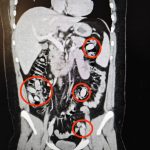

Yurtdışından Eskişehir’e gelen S.A. (25) isimli yabancı uyruklu şahsın kent girişindeki çevirme noktasında durumundan şüphelenilmesi üzerine hastanede yapılan detaylı tetkikler neticesinde yutmak suretiyle midesinde 44 kapsül metamfetamin maddesi taşıdığı anlaşıldı. Cerrahi müdahaleyle sözkonusu maddeler şahsın bedeninden çıkarıldı. Tedavisi akabinde şahıs tutuklandı. Yapılan titiz operasyon ile uyuşturucu maddelerin Eskişehir’de piyasaya sürülmeden ele geçirilmesi sağlandı.

Midesinde taşıdığı uyuşturucu maddeler polisin dikkatinden sayesinde ele geçirildi